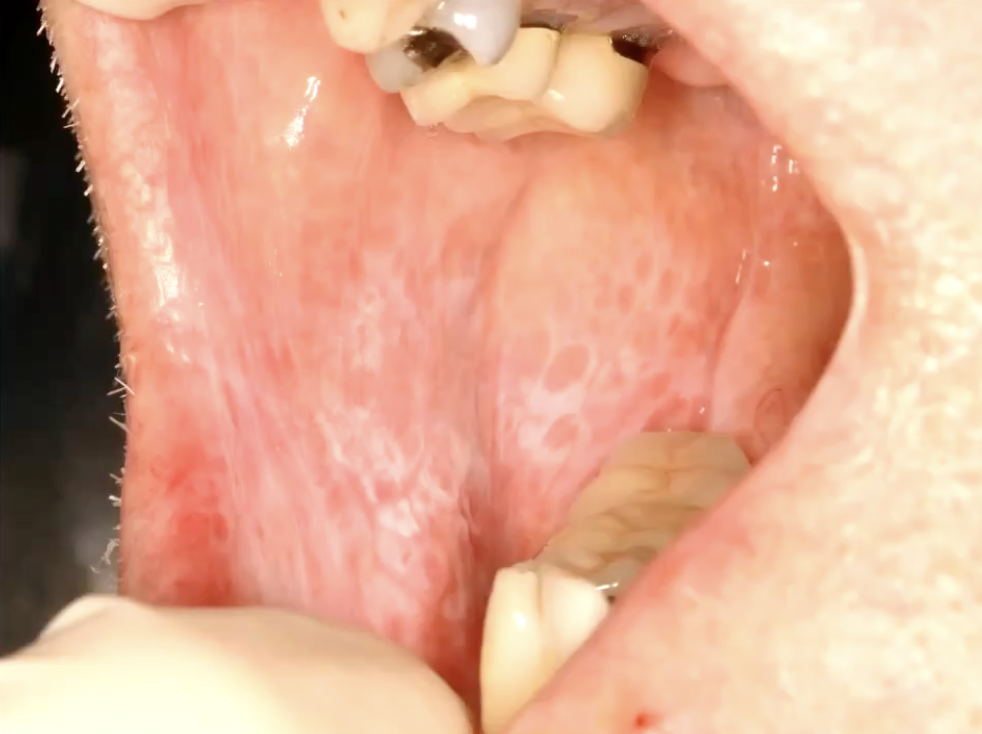

what condition?

• Often asymptomatic

• Posterior buccal mucosa

• Lacy white striations (Wickham striae)

• almost always bilateral

lichen planus reticular form